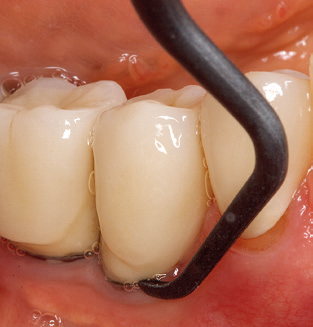

Das aktuelle Arbeitskonzept für die UPT

Die Aktualisierung der Anamnese stellt im Rahmen der UPT eine zentrale Maßnahme dar, sie sollte mindestens einmal jährlich erfolgen. Sie dient dazu, mögliche neue Risikofaktoren zu erkennen und zu dokumentieren. Vor allem dann, wenn ein Patient langjährig betreut wird, ist es wichtig, zu erfahren, ob sich patientenspezifische und allgemeinmedizinische Risikofaktoren verändert haben. Hier sollte an erster Stelle an ein erhöhtes Risiko durch Diabetes gedacht werden, aber auch andere allgemeinmedizinische Erkrankungen (kardiovaskuläre Erkrankungen und Neoplasien) können aufgrund der erfolgten Therapien und der notwendigen Medikamenteneinnahme zu einem veränderten Risikoprofil führen. Das Update der Anamnese ist also auch im Rahmen der UPT sehr wichtig, um gegebenenfalls aufgrund eines veränderten Risikoprofils eine Veränderung des Behandlungsintervalls zu veranlassen. Im nächsten Schritt ist es wichtig, der Diagnostik besondere Aufmerksamkeit zu schenken. Die Instrumentation ist zwar ein zentraler Bestandteil der UPT, in keinem Fall sollte sie aber Bestandsaufnahme und Dokumentation verdrängen. Für die Diagnose ist dabei der parodontale Befund unerlässlich, eine Zunahme der Sondierungstiefen und eine Erhöhung des BOP­Index sind zentrale Indikatoren für eine Progression parodontaler und periimplantärer Erkrankungen. Zum Erheben der benötigten Daten darf daher nicht davor zurückgeschreckt werden, auch Implantate zu sondieren. Dabei ist es wichtig, dass hierfür millimeterskalierte PAR­Sonden verwendet werden. Für die Sondierungsbefunde an natürlichen Zähnen haben sich seit Jahrzehnten metallische Sonden bewährt. Bei Implantaten ist die Herausforderung für das Erheben korrekter und reproduzierbarer Sondierungsbefunde größer. Da es durch die Diskrepanz von Implantatdurchmesser und Kontur der Suprakonstruktion regelmäßig zu einer Überkonturierung der Suprastruktur kommt, sind für Sondierungen an Implantaten flexible, aber dennoch millimeterskalierte Son­ den sehr sinnvoll (z. B. Colorvue Kit PCV11KIT6, Hu­Friedy; Abb. 4).

Abb. 4: Für das Sondieren an dentalen Implantaten sind biegsame, millimeterskalierte Sonden empfehlenswert (z.B. Colorvue Kit PCV11KIT6, Hu-Friedy). – Abb. 5a und b: Eine gerade Arbeitsspitze (1P, W&H Dentalwerk Bürmoos GmbH) ist universell für die Instrumentierung natürlicher Zähne geeignet. – Abb. 6: Für die Bearbeitung schwer zugänglicher Bereiche der Zahn- und Wurzeloberflächen (z.B. Furkationen) bieten sich gebogene Arbeitsspitzen (3Pr/3Pl, W&H Dentalwerk Bürmoos GmbH) an. – Abb. 7: Die spitz zulaufende sechseckige Implantatreinigungsspitze (1I, W&H Dentalwerk Bürmoos GmbH) ermöglicht eine atraumatische und effiziente Reinigung der Kronen- und Abutmentoberflächen. – Abb. 8: Für die manuelle Instrumentierung der Implantatoberflächen sind Titan- oder Carbonküretten geeignet.

Die gute Ausleuchtung des Arbeitsfeldes stellt eine wesentliche Erleichterung dar. Bei dem von den Autoren genutzten System ist dies gelungen, indem ein 5­facher LED­Ring in das Handstück integriert wurde. Natürlich werden für dieses System unterschiedliche Arbeitsspitzen für die jeweiligen Indikationsbereiche angeboten. Eine gerade, universell einsetzbare Spitze ist das Basisinstrument zur maschinellen Instrumentierung natürlicher Zähne (Abb. 5a und b). Für schwer zugängliche Bereiche im Seitenzahnbereich werden gebogene Spitzen angeboten, die auch einen Zugang zu freiliegenden Furkationen ermöglichen (Abb. 6).